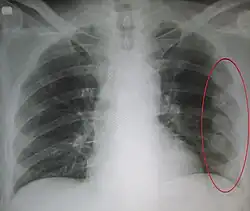

| An X ray showing multiple old fractured ribs of the person's left side as marked by the oval | |

Plain X-rays often pick up displaced fractures but often miss undisplaced fractures.[13] CT scanning is generally able to pick up both types of fractures.[13]